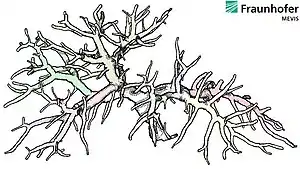

Fields of application, research projects

MeVisLab has been used in a wide range of medical and clinical applications, including surgery planning[16] for liver,[17][18][19][20] lung,[21][22] head[23][24] and neck and other body regions, analysis of dynamic, contrast enhanced breast[25][26] and Prostate MRI, quantitative analysis of neurologic[27] and cardiovascular image series,[28][29] orthopedic quantification and visualization, tumor lesion volumetry[30] and therapy monitoring,[31] enhanced visualization of mammograms, 3D breast ultrasound and tomosynthesis image data, and many other applications. MeVisLab is also used as a training and teaching tool[32][33] for image processing (both general and medical[34]) and visualization techniques.